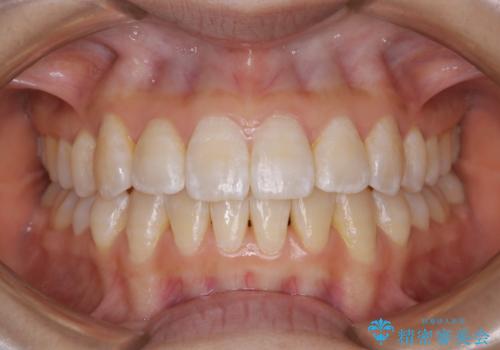

[ 前歯開咬 ] 前歯が噛んでいない マウスピース矯正治療

担当医 大元洋佑

![[ 前歯開咬 ] 前歯が噛んでいない マウスピース矯正治療の症例 治療後](https://seimitsushinbi.jp/wp/wp-content/uploads/2022/11/IMG_2488-500x350.jpg?v=1668218373)